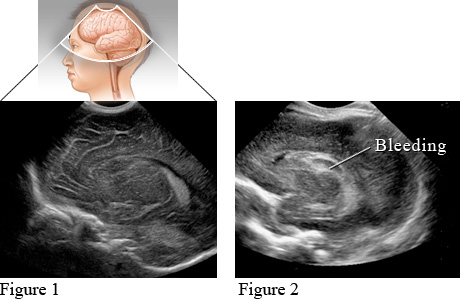

Cranial ultrasound uses reflected sound waves to produce pictures of the brain and the inner fluid chambers (ventricles) through which cerebrospinal fluid (CSF) flows. This test is most commonly done on babies to evaluate complications of premature birth.

Figure 1 shows a normal brain of a newborn baby. Figure 2 shows an area of bleeding in a premature newborn baby.